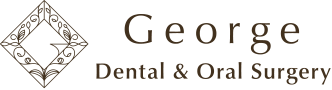

▶︎ 診断と治療計画

検査の結果、右下6番は保存が難しく、抜歯が必要な状態でした。

しかし、周囲の骨が大きく溶けていると、インプラント治療が難しくなることがあります。

そこで当院では、

🦴「ソケットプリザベーション」(抜歯窩の骨を守る処置)

という方法を選択しました。

抜歯と同時に骨補填材を入れ、

骨や歯ぐきの高さが大きく失われないように保護する治療です。

これにより、後のインプラント治療が大きく有利になります。

① 抜歯即時のソケットプリザベーションで骨を守る

→ 将来のインプラントが簡単&安全に

・ソケットプリザベーション(抜歯部に人工骨を入れて土台を守る処置) 40,000円